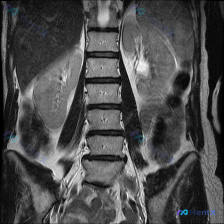

看到这份腰椎MRI的片子,整理了完整的读片和分析思路跟大家分享一下。 病例基本影像信息 这是一份腰椎矢状位T1加权MRI图像,图像质量清晰,没有明显运动伪影,显示了L1-L5全腰椎节段,还有部分胸腰结合部和骶骨: 1. 腰椎生理前凸存在,椎体排列规整,没有明显滑脱或侧弯 2. 各腰椎椎体形态正常,没...